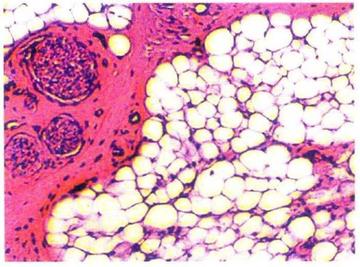

脂肪组织(英文名:adipose tissue),是含有大量脂肪细胞的结缔组织。[6]其以脂肪细胞为主要成分,聚集成团的脂肪细胞被疏松结缔组织分隔成小叶。[2][3]脂肪组织由胚胎时期的间充质演化而成,它是代谢活跃、功能复杂的内分泌器官。[3]

根据脂肪所在的分布区域可以将脂肪组织分为皮下脂肪和内脏脂肪。位于浅表的是皮下脂肪,位于深层的是内脏脂肪。[7]根据脂肪细胞的结构和功能不同,脂肪组织可分为黄(白)色脂肪组织和棕色脂肪组织。黄(白)色脂肪组织的脂肪细胞是单泡脂肪细胞;棕色脂肪组织的脂肪细胞是多泡脂肪细胞。[4]成年人的大多数脂肪组织属于黄(白)色脂肪组织,主要分布于皮下组织、网膜、肠系膜和黄骨髓等处。[3]棕色脂肪组织在新生儿中较多,新生儿主要分布在肩胛间区、腋窝及颈后部等处;成年人含量极少,在肾周围呈岛状分布。[2][3]脂肪组织具有储存和提供能量、内分泌调节、抗寒和维持体温、缓冲保护、支持填充等功能。[3][4][5]